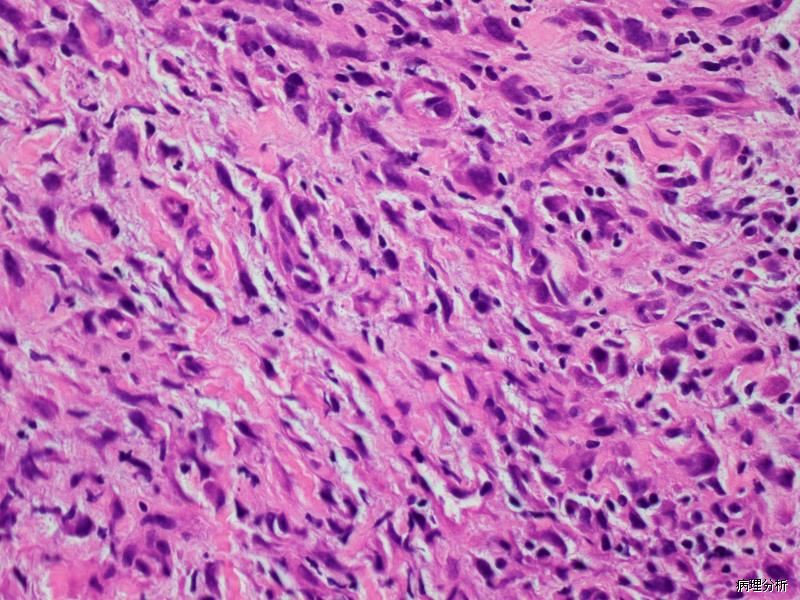

由大量增生的纤维母细胞、肌纤维母细胞、节细胞样细胞和形态上介于两者之间的过渡形细胞组成;

纤维母细胞、肌纤维母细胞呈梭形或胖梭形,也可呈蝌蚪状和不规则形,核膜厚,染色质呈空泡状,可见核仁,核分裂像多少不等,但无病理性核分裂;

间质含有多少不等的黏液样物质和胶原纤维;